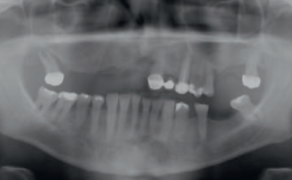

Pacjent zgłosił się do naszej kliniki, skarżąc się na ograniczenie czynności narządu żucia i nadwrażliwość zębów. Dodatkowo nie był zadowolony z wyglądu swoich zębów. W badaniu stomatologicznym stwierdzono rozległe zmiany próchnicowe i liczne wadliwe plomby. Na wszystkich zębach stwierdzono oznaki zaawansowanej erozji (fot. 1). Znacząca utrata tkanek zęba była szczególnie widoczna w zębach przednich. Analiza linii uśmiechu wykazała zaburzenia stosunku długości do szerokości. W trakcie naturalnego uśmiechu zęby pacjenta były prawie niewidoczne. Dodatkowo stwierdzono bardzo wyraźną niezgodność pomiędzy linią uśmiechu a linią środków łuków zębowych. U pacjenta stwierdzono znaczną utratę pionowego wymiaru zwarcia (OVD). Rozpoznano również zaburzenia czynnościowe (m.in. dysfunkcję czaszkowo-żuchwową). Celem leczenia było przywrócenie zębom proporcji, prawidłowego funkcjonowania oraz estetycznego wyglądu. Dlatego też konieczna była korekta wady zgryzu oraz wymiaru pionowego.